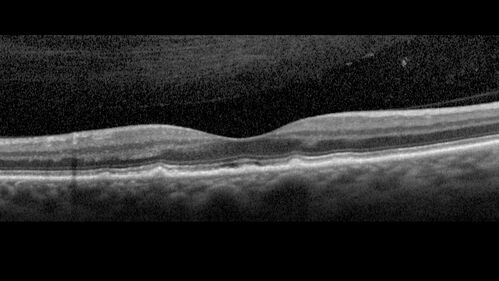

Large and Extensive Macular Drusen

64 year old female with 20/25 vision taking vitamins in for a checkup.